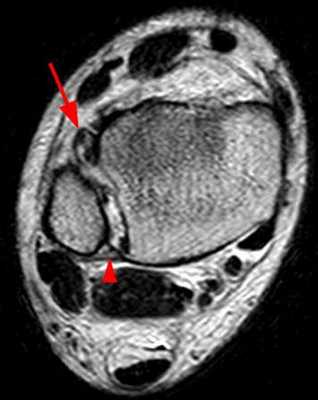

Ниже представлены срезы МРТ в которых наглядно показано расположение повреждённых связочных структур.

Данные повреждения практически в 100 % случаев пропускаются при первичном обращении в травмпункт. При несвоевременном или неадекватном лечении нестабильность голеностопного сустава приводит к разрушению суставного хряща, выраженной боли, деформации, и в конечном счёте к полной утрате функции опоры и ходьбы. В зависимости от того какие связки разорваны и от того насколько выражена нестабильность, артроз развивается в разные сроки, от 1 года при разрыве синдесмоза, до 20 и более лет при изолированном разрыве передней таранно-малоберцовой связки.